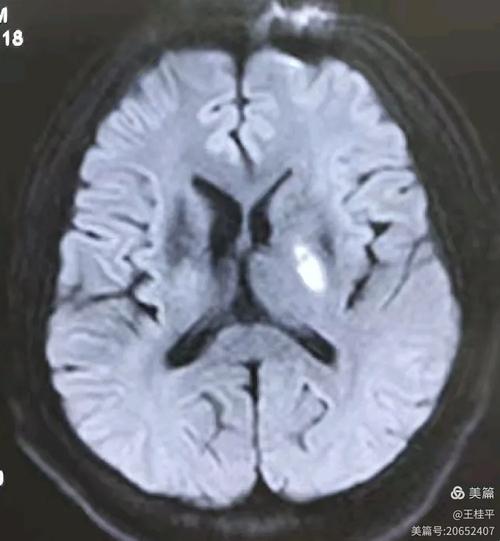

陈旧性脑梗死的MRI特点可以概括为 “长T1、长T2信号,信号均匀,边界清晰,无占位效应,可伴有脑萎缩和脑室扩大”。

- 信号特征: 典型的 “长T1、长T2” 信号,即T1WI上低信号,T2WI和FLAIR上高信号。

- 信号均匀性: 病灶内部信号通常非常均匀,不像急性期那样混杂。

- 边界: 边界清晰锐利,这是因为坏死组织已被完全清除,形成了明确的囊腔或软化灶。

- 占位效应: 无或极轻微,急性期脑水肿导致的脑组织移位(占位效应)在陈旧性病灶中已经完全消失。

- 穿支动脉(深穿支)梗死则表现为 基底节区或丘脑的圆形或卵圆形 小病灶。